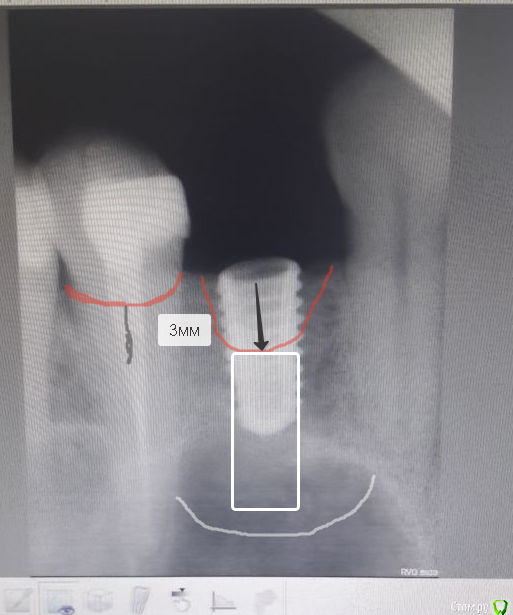

Sampson Опубликовано 15 июля, 2018 Поделиться Опубликовано 15 июля, 2018 Обоснуйте пожалуйста Ваше мнение по поводу выкручивания, сделать контрольный рентгенснимок и если кость не уходит может быть стоит оставить 2мм кости ушло осталось 6 мм импланта в кости, На которые установлена коронка и абатмент.от 12милиметрового импланта яб еще ожидал борьбы за жизнь. И второй момент самая бурная резорбция идет до года.Потом кость стабилизируется. Вслучае если собрались ждать сделайте через месяца 2 времянку. На год. И наблюдайте. Но разве не проще выкрутить болт и провести НКР? Ссылка на комментарий

Bier Опубликовано 17 июля, 2018 Поделиться Опубликовано 17 июля, 2018 Имплант установлен вровень с костью, это был предпоследний снимок, потом было проведено докручивание. По КТ место было 7,79, поэтому был выбран имплантат 8 мм и закручен бикортикально. Что было не верноНеверно было все.Игорь, я вам очень рекомендую если не начать протезировать самому, то по крайней мере подружиться поближе со своим ортопедом и посмотреть на эстетический результат протезирования.Сейчас вы своим вопросом выдаете в себе хирурга, который совершенно не представляет, как будет выглядеть коронка на вашем имплантате. При выборе позиции имплантата ориентироваться нужно не на кость, а на зенит будущей коронки. От которой нужно отступить минимум 2,5мм, а для конического имплантата 3-4мм. 2 Ссылка на комментарий

Иван911 Опубликовано 17 июля, 2018 Поделиться Опубликовано 17 июля, 2018 Неверно было все.Игорь, я вам очень рекомендую если не начать протезировать самому, то по крайней мере подружиться поближе со своим ортопедом и посмотреть на эстетический результат протезирования.Сейчас вы своим вопросом выдаете в себе хирурга, который совершенно не представляет, как будет выглядеть коронка на вашем имплантате. При выборе позиции имплантата ориентироваться нужно не на кость, а на зенит будущей коронки. От которой нужно отступить минимум 2,5мм, а для конического имплантата 3-4мм. Igor.pngДоктор, со схемой вы конечно перегнули, но текст правильный). думаю что стоит добавить - конус конусу рознь. Корейский конус желательно заглубить на 1 мм. 2 Ссылка на комментарий